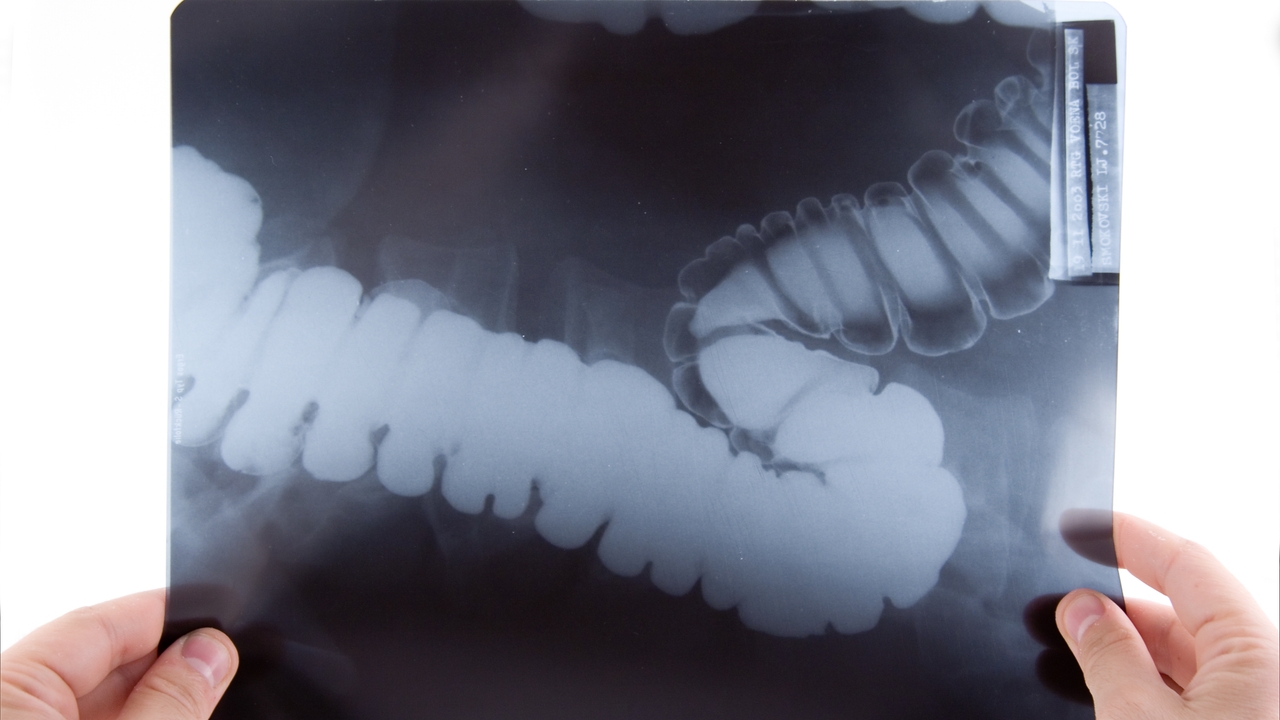

El cáncer colorrectal ha experimentado un preocupante aumento de su incidencia entre adultos menores de 50 años, una tendencia confirmada por un reciente estudio publicado en la revista «JAMA». Aunque la mortalidad por cáncer en esta franja de edad ha disminuido en general, el cáncer colorrectal se ha convertido en el tumor más letal, alertando a la comunidad médica sobre la necesidad de estrategias efectivas de prevención y detección.

Tradicionalmente, el cáncer colorrectal ha sido considerado una patología de las personas mayores, con una edad media de diagnóstico cercana a los 70 años. Sin embargo, en las últimas dos décadas, su incidencia ha duplicado en adultos jóvenes, transformándose del quinto al primer lugar en mortalidad por cáncer en estadounidenses menores de 50 años. Este aumento ha llevado a una preocupación significativa, ya que actualmente más del 60% de los diagnósticos en esta población se realizan en etapas avanzadas (III o IV), lo que limita las posibilidades de tratamiento y reduce las tasas de supervivencia.